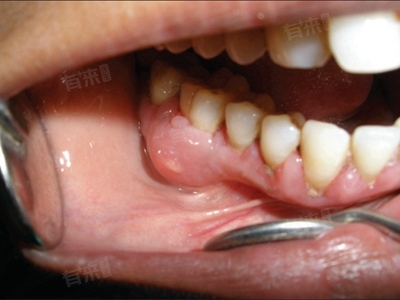

牙龈出现白色溃烂是一种常见的口腔问题,可能由多种疾病引起,如创伤性口腔溃疡、牙龈炎等,建议此类患者及时采取药物治疗等,继而促使病情好转。

4、牙龈炎:牙龈炎是牙龈组织的炎症性疾病,主要由牙菌斑引起,当牙菌斑长期刺激牙龈时,可导致牙龈红肿、出血、疼痛,严重者可出现牙龈溃烂。患者要加强口腔卫生,若炎症严重,需遵医嘱口服抗生素,以控制感染。